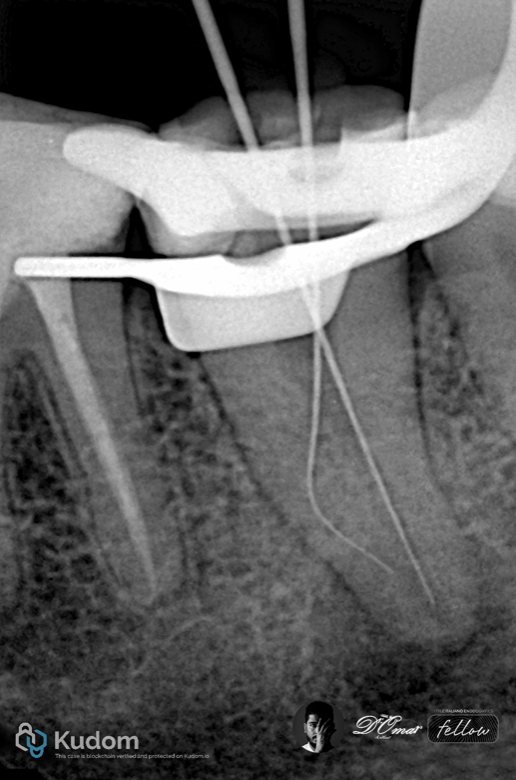

Fig. 1

Two-Canal Mandibular Molars

Two-canal mandibular molars typically consist of one mesial and one distal canal, often with round or oval cross-sections. These canals are usually wide, relatively straight, and accessible, allowing efficient mechanical shaping and irrigant penetration.

Radiographic examination showed a well-defined periapical radiolucency

Diagnosis

Necrotic pulp

Chronic apical periodontitis

Anatomy

Access revealed:

One mesial canal

One distal canal in one apical foramen

Working length established using apex locator and radiographs